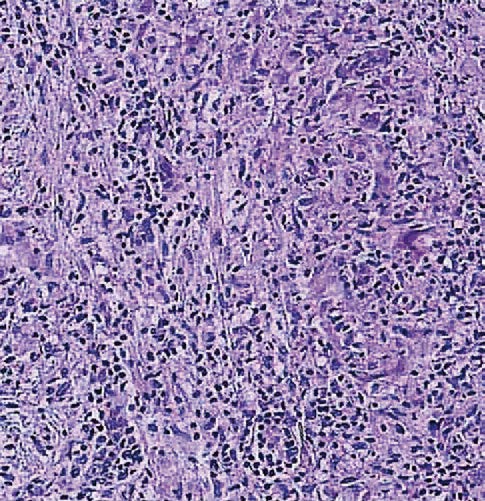

Dal punto di vista istopatologico, il granuloma sarcoideo rappresenta l’unità funzionale della malattia. Esso è costituito da un raggruppamento organizzato di cellule infiammatorie, principalmente macrofagi attivati che assumono un aspetto epitelioide e possono fondersi per formare cellule giganti multinucleate, come le cellule di Langhans.4

Questi aggregati sono tipicamente circondati da una corona di linfociti, con una netta prevalenza di linfociti T helper CD4+, e in misura minore da linfociti B e plasmacellule.5 Un elemento discriminante fondamentale rispetto alla tubercolosi è l’assenza di necrosi caseosa centrale, sebbene in rari casi possano essere presenti minime aree di necrosi fibrinoide.

La dinamica di formazione del granuloma suggerisce un processo di compartimentazione immunitaria, in cui l’organismo tenta di isolare un antigene persistente e non degradabile. Se il processo infiammatorio non si risolve, la persistenza delle citochine profibrotiche prodotte dai macrofagi e dai linfociti Th2 può indurre una transizione verso la fibrosi, portando alla distruzione dell’architettura tissutale originale e alla perdita della funzione d’organo, come osservato nellostadio IV della sarcoidosi polmonare.6 7